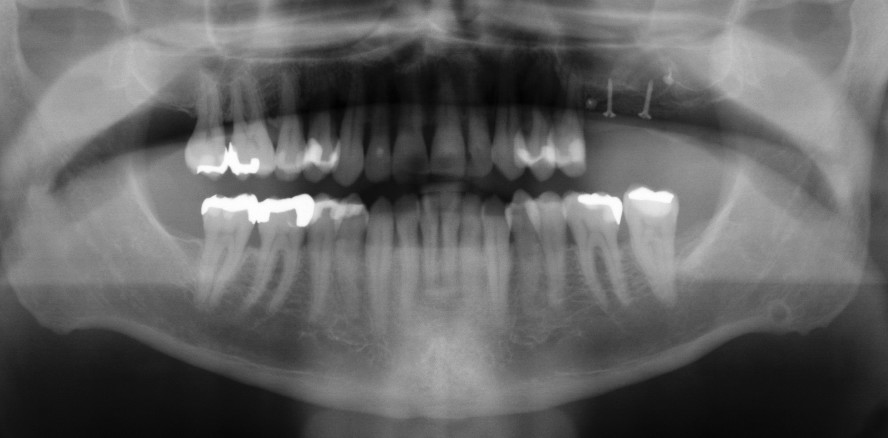

Ein 51-jähriger Patient, Nichtraucher, stellte sich nach unterschiedlichen Parodontaltherapien alio loco mit einer ausgeprägten sowie aggressiven Parodontitis1 und mit einseitiger Freiendsituation im linken Oberkieferseitenzahnbereich vor. Folgender Fachbeitrag beschreibt, wie durch umfangreiche parodontale Maßnahmen der kompromittierte Zustand letztlich durch Transplantation eines allogenen Knochenblocks parodontologisch und implantologisch rehabilitiert werden konnte (Abb. 1).

Nach umfangreicher Befund- und Screeningerhebung sowie nach mikrobiologischer Keimbestimmung (Labor Dr. Hauss, Kiel; Tab. 1) und radiologischer Untersuchung (Abb. 2) erfolgte 2015 zunächst die nichtchirurgische Parodontitistherapie im Sinne einer geschlossenen Kürettage.